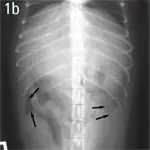

Figure 1. Crescent and triangular areas of free intraperitoneal gas (arrows) are shown that do not correspond to the tubular-shaped pattern of gas seen in the small intestine.(A) Lateral view, above. (B) Ventrodorsal view

Figure 4. Triangular-shaped gas opacities underneath the caudal ribs and extending along the abdominal wall (horizontal-beam image). Erosion of the intestinal adenocarcinoma with subsequent perforation was noted at surgery.